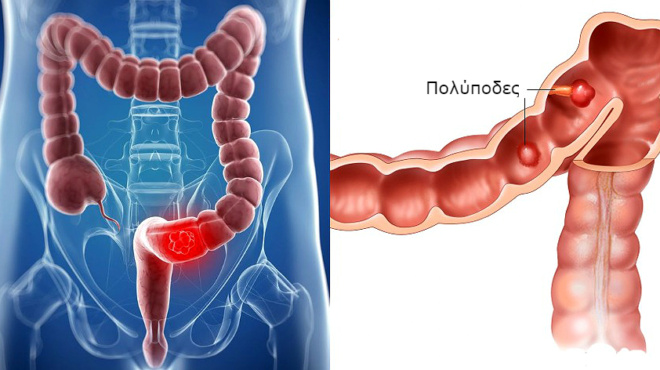

Καρκίνος στο στομάχι, τα έξι “αθώα” πρώιμα συμπτώματα. Ο καρκίνος του στομάχου είναι μία νόσος κατά την οποία τα στομαχικά κύτταρα γίνονται κακοήθη (καρκινικά) και αυξάνονται ανεξέλεγκτα, σχηματίζοντας όγκο. Πρόκειται για την πέμπτη πιο διαδεδομένη μορφή καρκίνου στην Ευρώπη. Τέταρτη παγκοσμίως και έβδομη στην χώρα μας. Προσβάλλει συχνότερα τους άντρες συγκριτικά με τις γυναίκες και συνήθως σε ηλικίες μεταξύ 60-80 ετών.

Το αδενακαρκίνωμα εντοπίζεται τουλάχιστον στο 90% των περιπτώσεων σε ασθενείς με καρκίνο του στομάχου. Σημειώνεται πως το υπόλοιπο 10% αποτελούν άλλοι τύποι καρκίνου του στομάχου όπως: